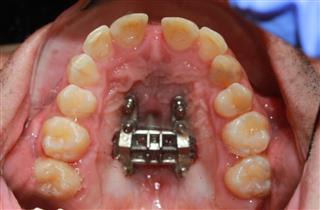

MSE treatment targets patients who are experiencing dental crowding, crossbites or breathing difficulties due to an underdeveloped maxillary arch. The procedure utilizes a specially designed device that is placed in the roof of the mouth. This device gently expands the maxillary bone over time, which is essential for promoting proper alignment and function of the jaw and teeth.

MSE treatment begins with the installation of a custom-designed expander that fits securely against the upper palate. Over the course of the treatment, this device is carefully adjusted to gradually widen the upper jaw. Throughout this period, our orthodontist and team will ensure that the process is comfortable and effective through regular monitoring and adjustments at our office.